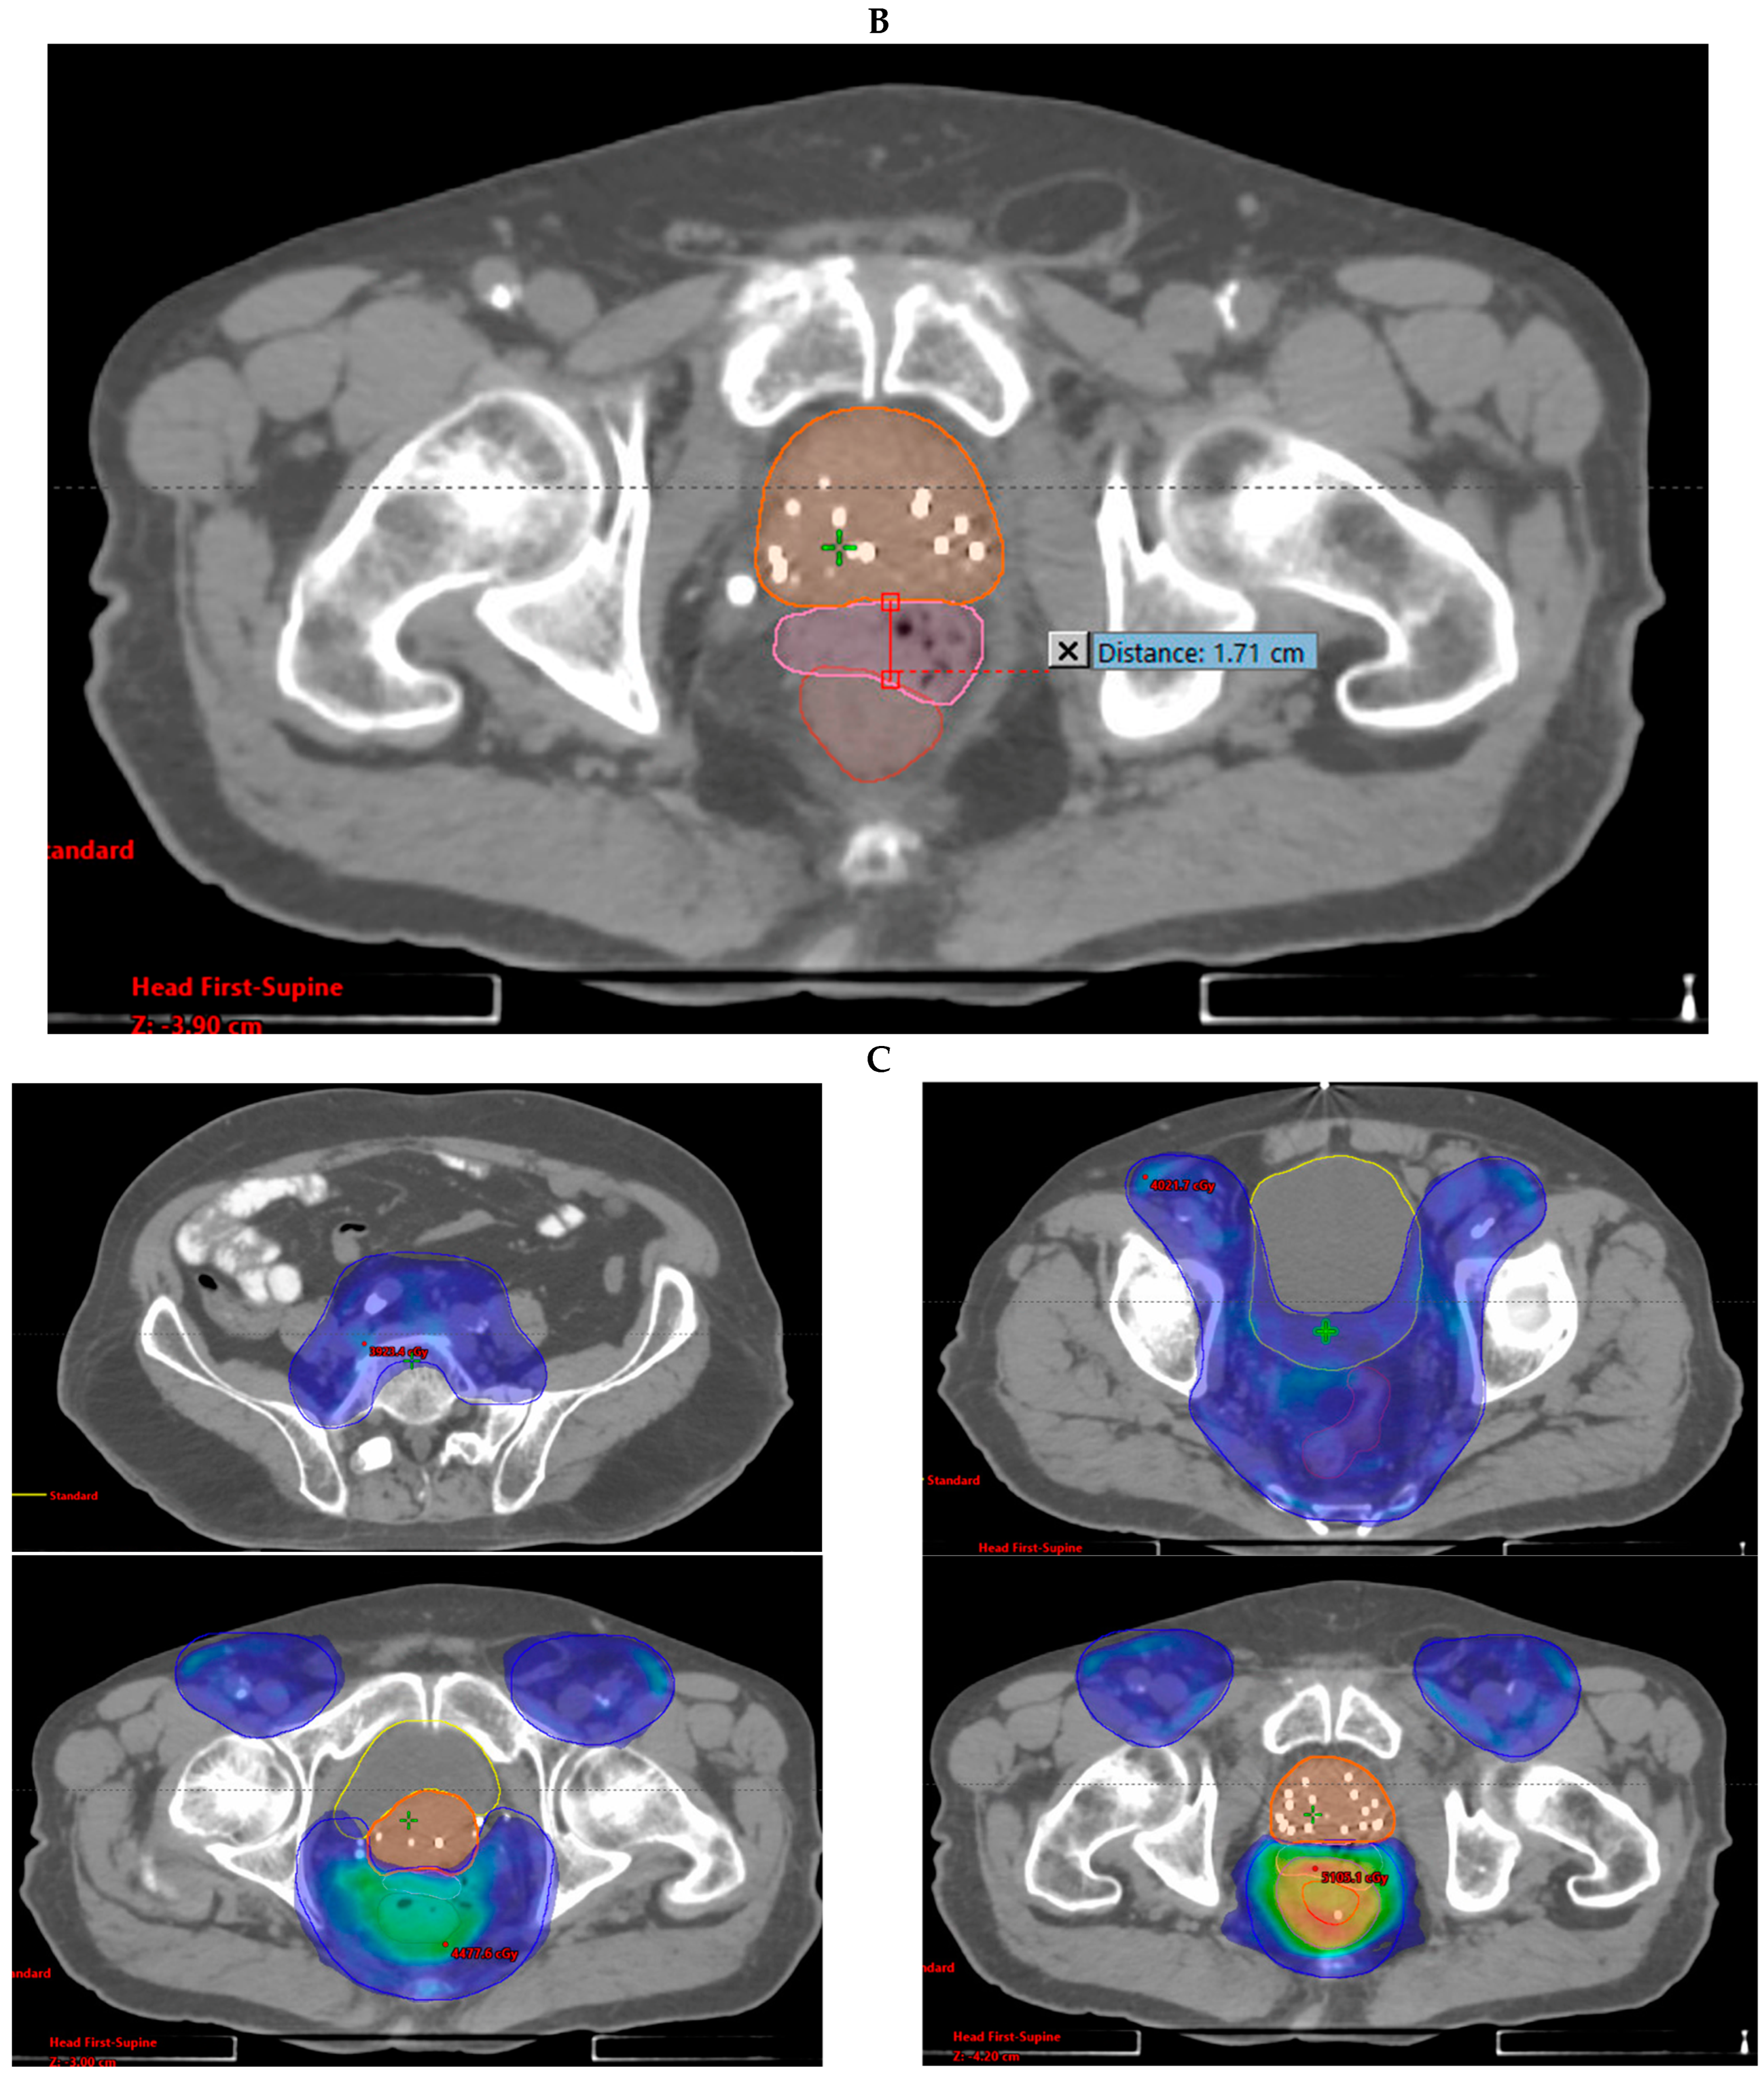

3.1. Case Report 1: Anal Squamous Cell Carcinoma

| Anal | 2006: -LDR | 2018: -Anal canal + LNs 36–48 Gy/24 fx QD | -POD; liver -CR; local | NED | No POD | 2 mo; liver treated with SBRT | 48 mo |

| Disease | GTV V100% | PTV V100% | Mean Rectal Dose (cGy) | Mean Bladder Dose (cGy) | Max Distance of Spacer (cm) |

|---|---|---|---|---|---|

| Anal | 100% | 96% | 4024.7 | 2730.1 | 1.71 |